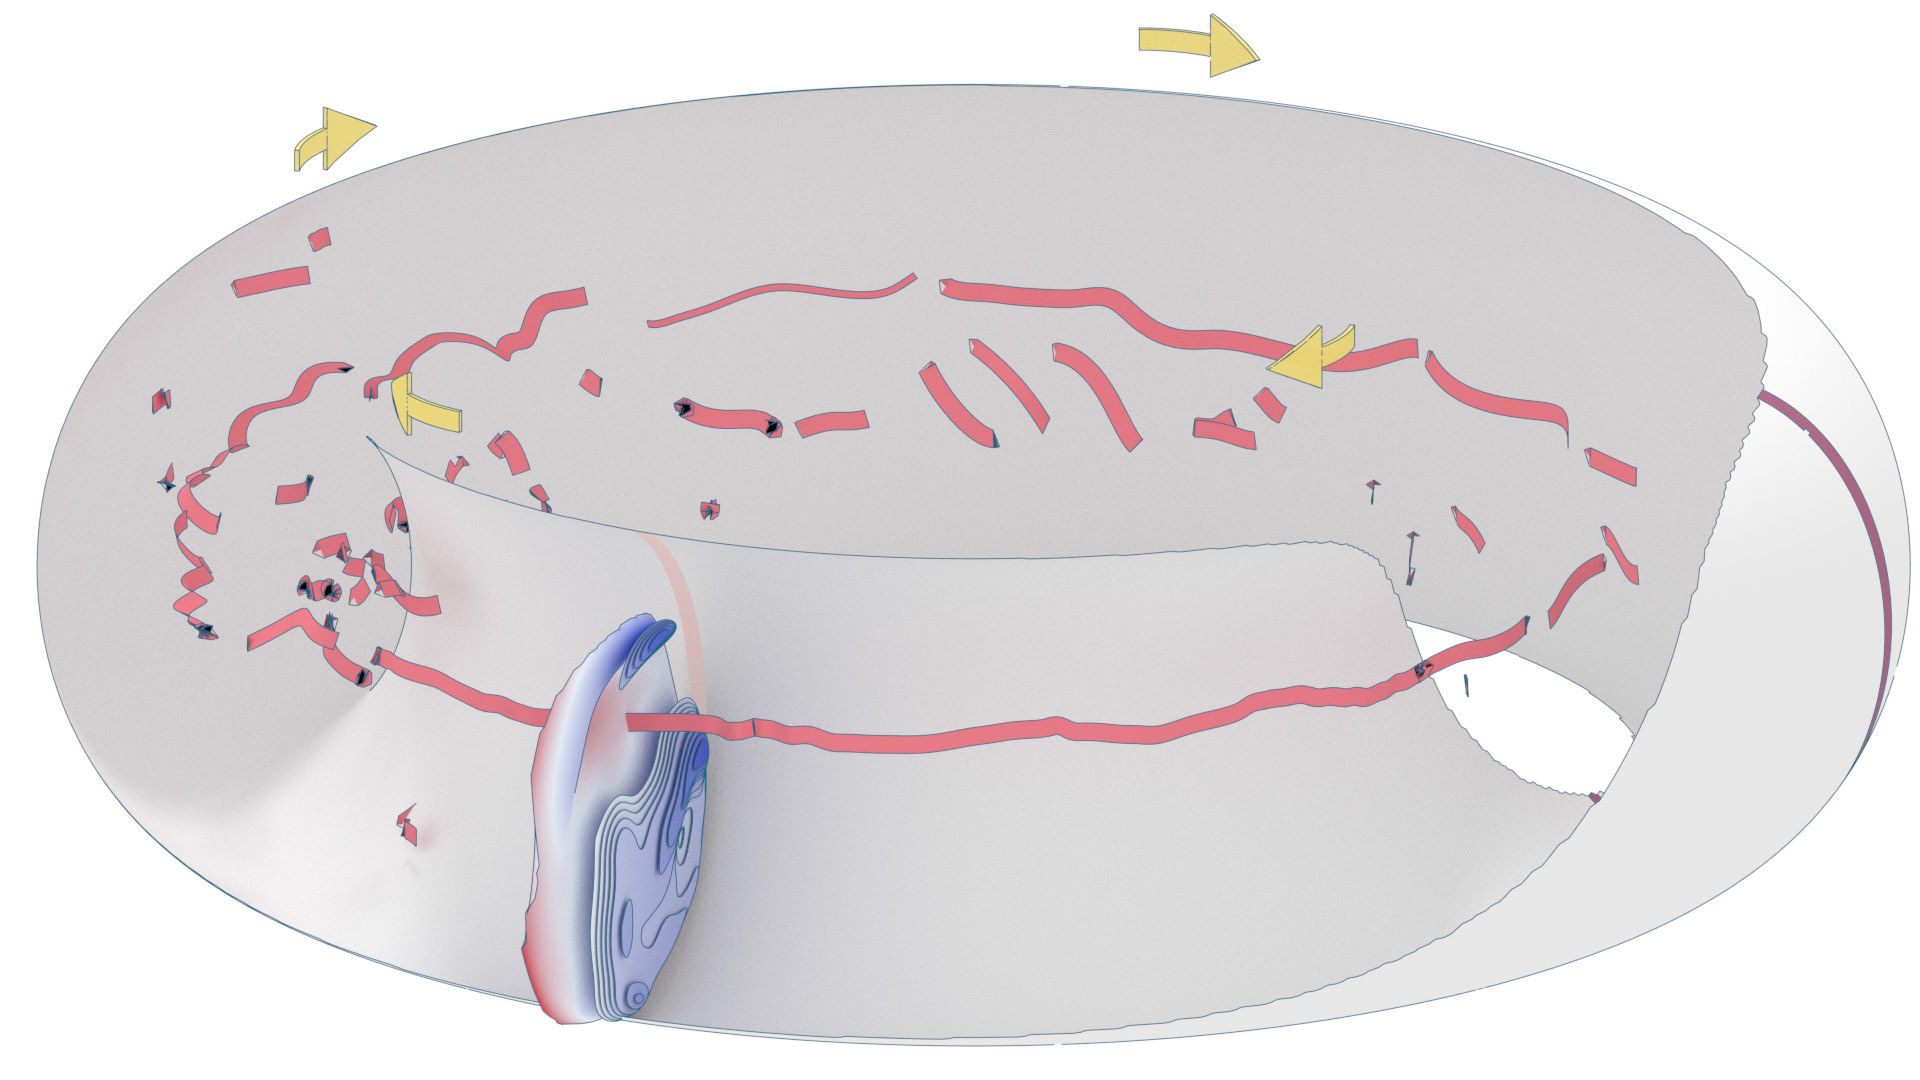

An ongoing collaboration with the Biomedical Simulation Lab (BSL), University of Toronto. In my role, I develop concept sketches and renderings that are then implemented algorithmically. The overall approach is to show turbulent flow visualizations without animation my mapping the transitions among states to carousel that corresponds to the cardiac cycle.